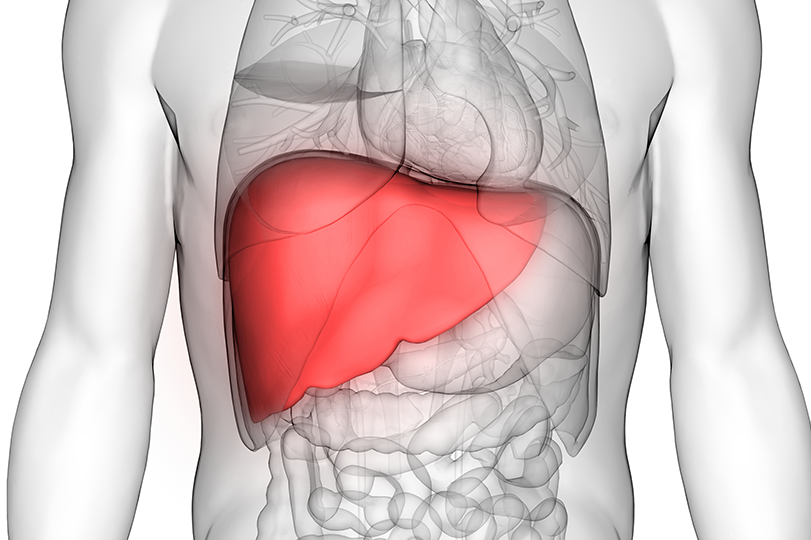

Few plants from Romania’s flora have attracted the attention of researchers as much as milk thistle (Silybum marianum). Considered a true green pharmacy for the liver, this modest plant, which grows spontaneously in sunny fields and meadows, has immense therapeutic power. Due to its high content of silymarin, milk thistle protects, detoxifies, and regenerates liver cells, also helping to cleanse the blood of toxins, heavy metals, and metabolic residues. In recent years, multiple clinical studies have confirmed that standardized extracts of milk thistle can support liver functions even in cases of severe liver diseases.

The main active substance, silymarin, stimulates protein synthesis at the level of liver cells, promoting their regeneration. It forms a protective layer on cell membranes, preventing the penetration of toxins and harmful substances. At the same time, it helps the liver produce new healthy cells, compensating for losses caused by alcohol, medications, or an unbalanced diet. Through this mechanism, the liver gradually regains its normal filtering and detoxifying functions.

Chronic inflammation of the liver (caused by viruses, alcohol, or toxins) is significantly reduced by administering extracts of milk thistle. Studies have demonstrated that the plant inhibits the release of inflammatory mediators, helping to reduce pain and restore tissues. In cases of hepatitis, it contributes to lowering transaminase levels.